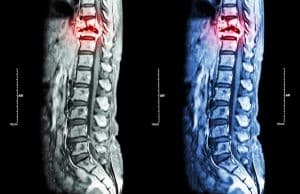

The National Institute of Neurological Disorders and Stroke defines a spinal cord injury as “damage to the tight bundle of cells and nerves that sends and receives signals from the brain to and from the rest of the body.” Your spinal cord can be found along your back, extending from your brain to your lower back. Injuries to the spine often happen when a person is involved in an accident, such as a car accident, truck accident, motorcycle accident, bicycle accident, pedestrian accident, and more. However, they can also be caused by violence and physical assault.

When a person is diagnosed with a spinal cord injury, they are often monitored for secondary health complications. The spinal cord injury is directly caused by the accident and injury, but the secondary health complications are caused by “swelling and inflammation” that comes from the injury. In other words, there would be no secondary complications if the spinal cord injury never occurred.